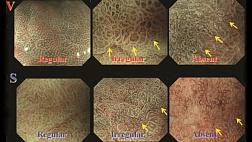

• эндоскопическое лечение раннего рака (эндоскопическая резекция слизистой оболочки, различные способы абляции (девитализация) опухоли);

Особое внимание уделяется технике выполнения полипэктомии, эндоскопической резекции слизистой и эндоскопическому гемостазу, как наиболее широко распространённым в клинической практике способам лечебного воздействия, осуществляемым через эндоскоп, при которых используются все виды хирургических энергий, включая механическое воздействие (эндоклипирование).